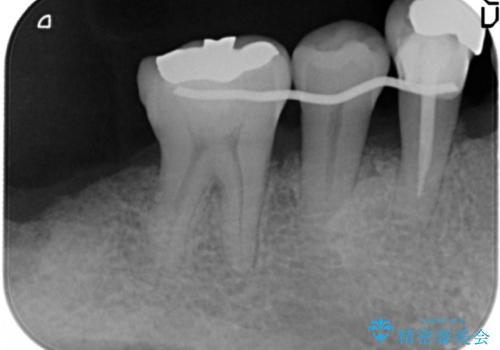

骨を再生させて歯周病を治す 再生療法 50代男性

- 全顎的な重度歯周病の患者様です。

骨吸収の進行している右下臼歯部に、再生療法(骨を増やす手術))を行いました。

再生療法から1年後、リエントリー手術により骨の再生を確認し、骨外科処置(骨を平らにして歯周ポケットの根本的な改善を図る処置)を行いました。

埋伏していた親知らず、保存不可能な右下の一番奥の歯(右下7)、状態の悪い犬歯(右下3)は抜歯しております。

再生療法と骨外科処置により、歯周ポケットは全周2mm以下となりました。